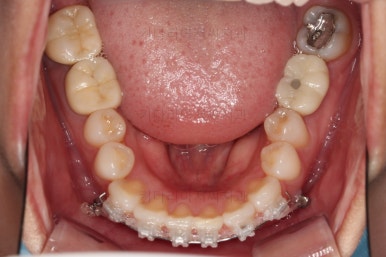

이번 환자분은 아래 앞니의 높낮이도 맞춰줘야해서 미니스크류까지 이용한 상황이었으나 6개월 정도 걸려서 비교적 발리 마무리 될 수 있었어요.

조금더 디테일을 조절하고 부산부분치아교정 마무리를 합니다.

전후 사진을 비교해 볼게요.

6개월만에 부산부분치아교정 완료했어요.

치열도 가지런해졌고, 웃는 모습도 매우 좋아졌네요.

이상 미니스크류, 미니튜브 등을 이용해 앞니를 부산부분치아교정 했던 치료사례였습니다.